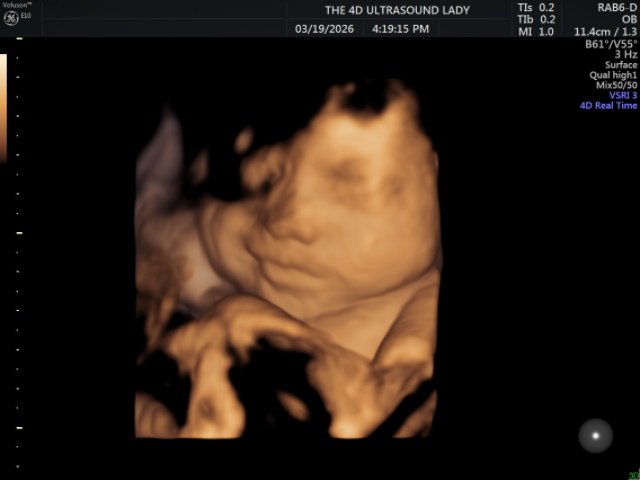

This month, our transfer process looked a little different, which caused a portion of our support to be delayed. While it should arrive next month, this has made the current month especially challenging. As we prepare for the baby’s arrival, there are several additional expenses, which makes this season feel even tighter. We would greatly appreciate prayer for wisdom as we make financial decisions and seek to be good stewards of what we have. We are also trusting the Lord for provision, especially with the upcoming costs of the birth, as well as the paperwork and embassy visits required for Presley’s birth abroad and passport. - My Birth

Please pray for a healthy delivery for both mom and baby. Our hope is for a smooth and natural birth, but above all, we are praying for safety and health for both of us. - Energy for Both of Us